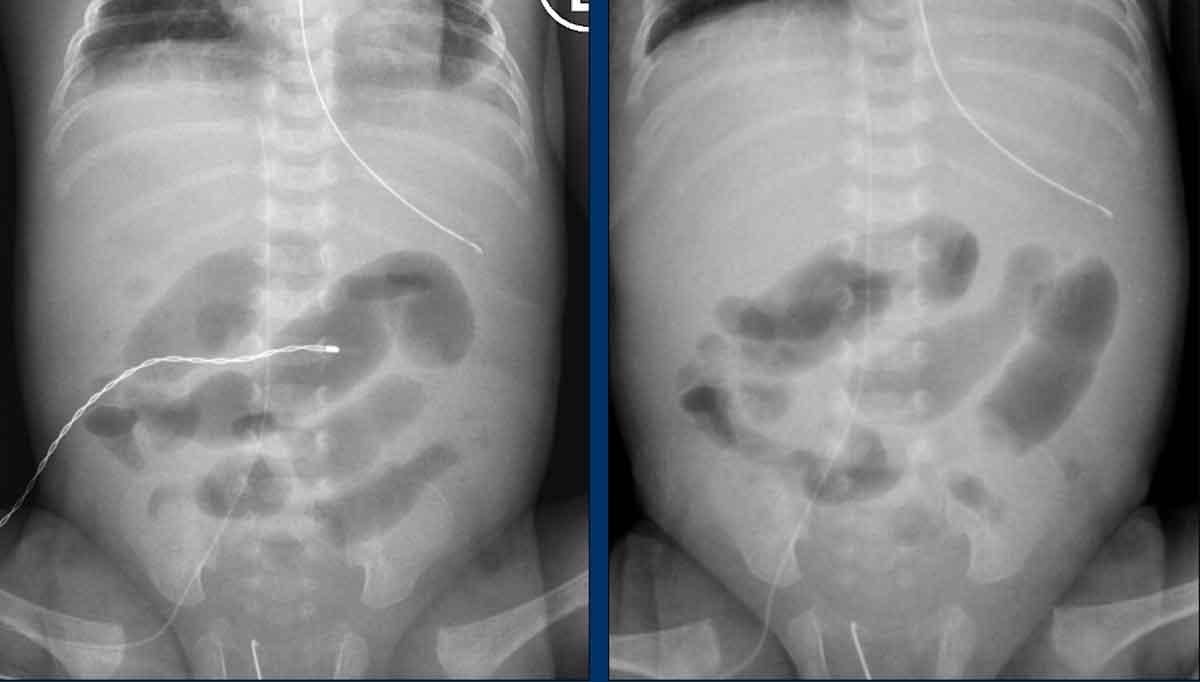

Hình ảnh

X-quang bụng cho thấy các quai ruột giãn và phân bố hơi không đều với vùng thiếu hơi ở góc phần tư dưới phải.

Hai phim X-quang chụp cách nhau vài giờ cho thấy ở vùng bụng trên chỉ có các quai ruột giãn nhẹ nhưng không có nếp niêm mạc, không thay đổi theo thời gian. Đây là dấu hiệu của vắng mặt nhu động ruột.

Lịch chụp lại được khuyến cáo là mỗi 6-8 giờ, nhưng tất nhiên phụ thuộc vào tình trạng lâm sàng.

Một ví dụ khác về quai ruột cố định.